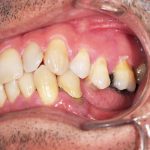

Arcade mandibulaire avant traitement orthodontique, séquelles de maladie parodontale

Après traitement orthodontique et réalisation d’une attelle fibrée (courtoisie Dr Patrick Fournier)

Arcade maxillaire avant traitement orthodontique, séquelles de maladie parodontale

Après traitement orthodontique et réalisation d’une attelle coulée collée (courtoisie Dr Patrick Fournier)